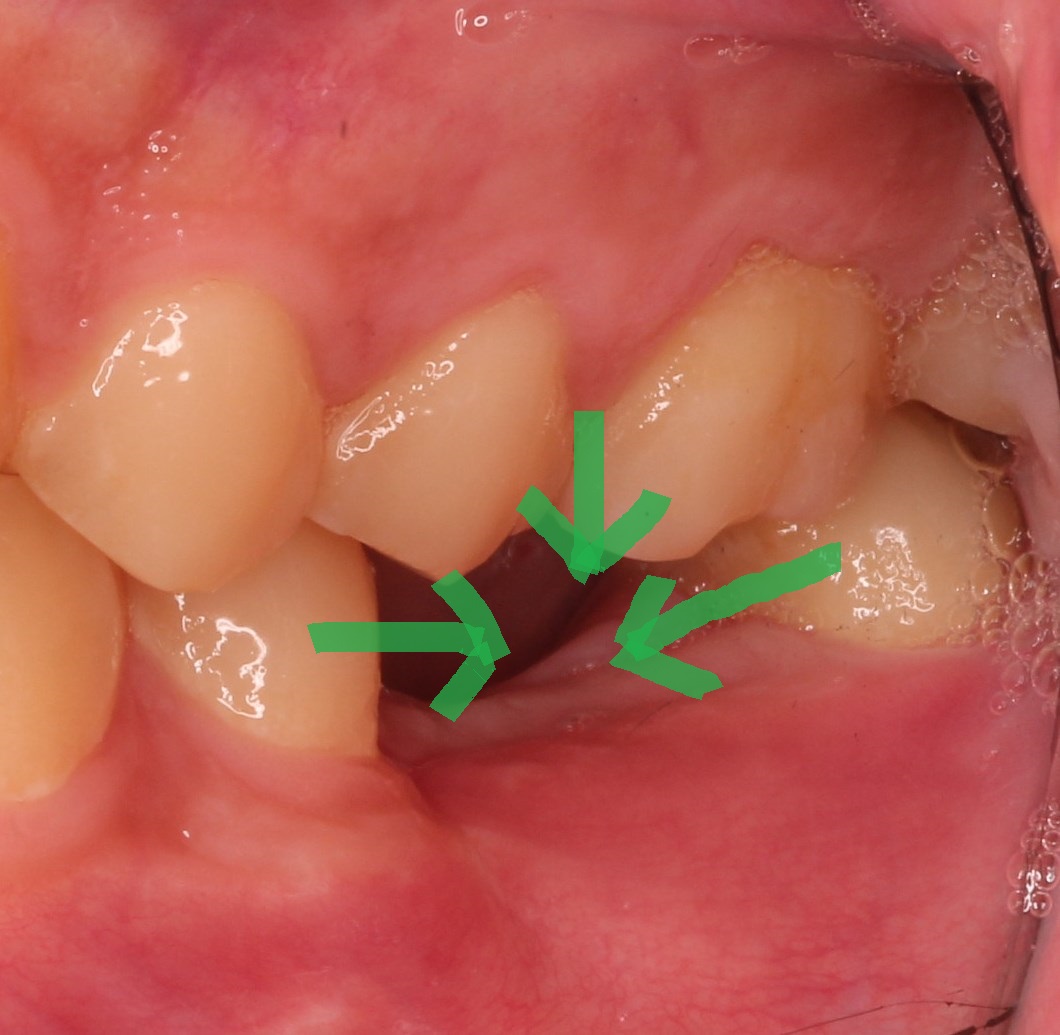

隣り合うは欠損側に倒れてきますし、向かいあう歯は伸びてきます。

簡単に言うと、歯が失われた部分を埋めるように歯が動きます。

この動くスピードはとてもゆっくりであることが多く、気づかないのですが、

歯が動くことで、歯の隙間ができたり、汚れが溜まりやすくなったり、

磨きにくくなったりします。

その一例ですが、歯が伸びることで、汚れや歯石が付着したりします。

これを戻すことは非常に難しく、新たに歯を抜かなければならない可能性が

出てきたりします。また、伸びることで歯並びが不揃いになることで、治療が

難しく、時間がかかることになります。

個人差がありますが、全体的に歯の隙間ができることもあります。